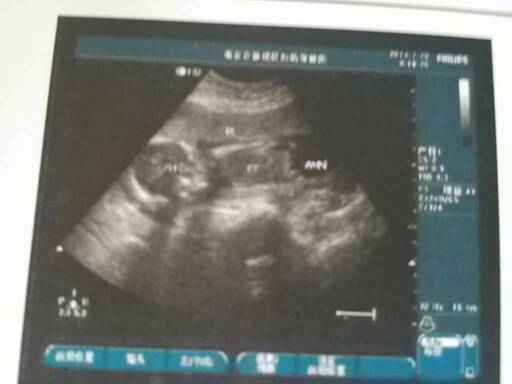

18周,医生可以看出来胎儿性别吗??我无所谓男宝女宝,只是特别好奇 18周,医生可以看出来胎儿性别吗??我无所谓男宝女宝,只是特别好奇。。 点击展开 宸宸宝贝萌萌哒✔ 2014-07-25 14:01 为您推荐: 其他回答 在怀孕的十六周后,可以使用彩超或者B超进行检查,通过观察胎儿的生殖器判断胎儿的性别。但是医院进行鉴定属于不合法的行为。 shenglongxiao 2014-07-25 14:02 相关问题 90天能知道胎儿性别没?好想知道 头胎是男宝 虽说男宝女宝健康就好 但好奇心还是有的 哪位医生帮我看看,这是18周的时候的B超,是否有什么问题没有啊?